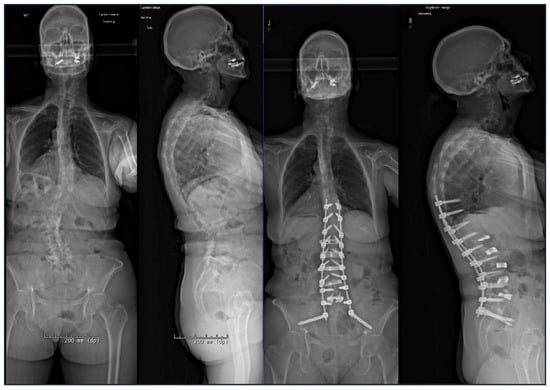

2.7. Custom Patient-Specific Rods